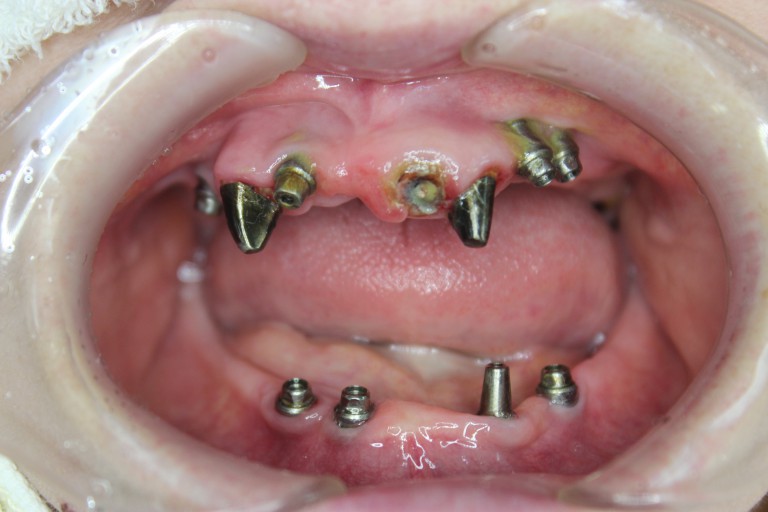

千差万別です。インプラント(上部)をはずしてみるとそんな患者さんの特徴が

垣間見えたり・・(笑)

インプラント上部を外した状態